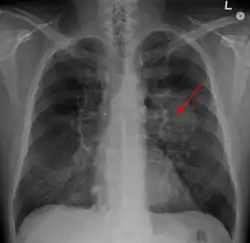

A chest X-ray showing a tumor in the lung (marked by arrow) | |